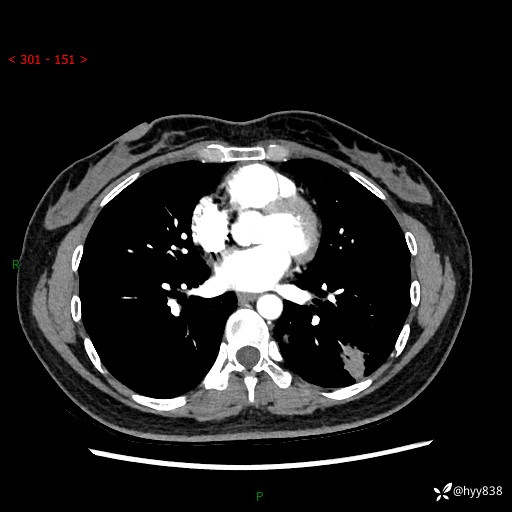

【患者信息】:36岁/女

【主诉】:左侧下胸部阵发性疼痛2周,乏力1周

【现病史及既往史】:患者自诉2周前饮酒后出现左侧下胸部阵发性疼痛,不随呼吸改变,无咳嗽咳痰、头晕头痛、咳血、呼吸困难等不适,于当地第一人民医院查胸部CT提示肺部感染,随后前往我院门诊给予抗感染(左氧氟沙星)治疗1周,自诉胸痛较前好转,感乏力、头晕,偶尔干咳,无咳痰,无发热、畏寒、胸闷、咯血、四肢酸痛、腹泻、腹痛等不适,门诊复查胸部CT提示:左肺下叶感染,病灶较前增加增大,遂以“肺部感染”收入我科。 起病以来,患者精神、饮食、睡眠可,大小便正常,体力体重无明显变化。

【检查】:胸部CT增强(外院平扫)